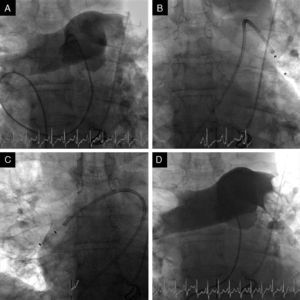

Case 3A 47-year-old woman, obese and with peripheral venous insufficiency, was admitted to the emergency room with syncope, sudden-onset dyspnea, epigastric pain, severe respiratory failure and shock. She had begun taking oral contraceptives three days previously. A few minutes after admission she suffered CPA with pulseless electrical activity and ALS was begun. Spontaneous return of circulation occurred several times but was immediately followed by CPA. TTE showed dilatation of the right chambers (Figure 3A), grade III/IV tricuspid regurgitation (pulmonary artery systolic pressure 45 mmHg above central venous pressure), pulmonary flow suggestive of PH and impaired RV systolic function.

Given the suspicion of obstructive shock due to high-risk PE, intravenous thrombolysis was performed with a 50-mg bolus of alteplase, which resulted in spontaneous permanent return of circulation after around 45 min of ALS. Thoracic CT angiography showed thromboembolic foci in the distal portion of both pulmonary arteries, in the origin of several lobar arteries, and most noticeably in the segmental branches of the right lower lobe artery (Figure 2). As the setting of shock remained refractory to supportive measures, it was decided to perform RT using the AngioJet® system, which resulted in immediate hemodynamic improvement and partial angiographic improvement. The patient remained under ventilatory and inotropic support for 10 days, followed by a favorable clinical course and complete neurological recovery. TTE performed one month after the acute event showed no RV dilatation or dysfunction or signs of PH (Figure 3B). The patient was discharged after 37 days.